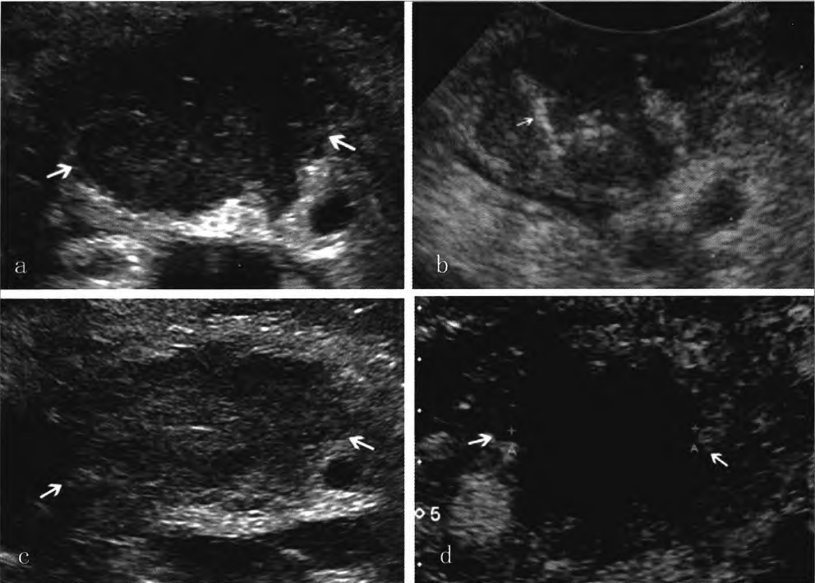

短期疗效:术前以右上腹痛就诊的15例胰腺癌,1例(6.7%)术后疼痛无明显缓解,再次行腹膜后神经节无水乙醇注射术,余14例(93.3%)一周内疼痛均有所缓解。13例胰腺恶性肿瘤患者术前CA-199升高,术后1个月7例(53.8%)CA一199降低,1例(7.7%)无明显变化,5例(38.5%)轻度升高。2例肝癌患者术后肿瘤标记物均较术前降低。术后1个月增强CT显示消融灶范围大于术前肿瘤范围,消融灶内见无增强区,部分病例周边出现轻度增强带,消融灶周边大血管管腔内充盈完整(图1)。

(图1局部进展期胰腺癌纳米刀消融前后超声图)